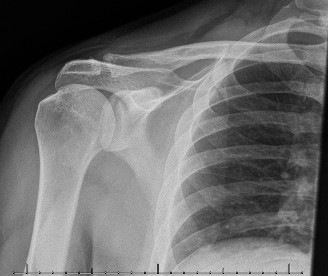

The challenges associated with treating an in-season athlete? CASE 12 A 28-year-old, recreational athlete presents to your clinic with shoulder pain and a history of multiple subluxations in the past. He describes a recent frank dislocation that had to be “popped” back in place on the field. His imaging is shown below (Fig. 2–34).

Figure 2–34

The correct answer is (A). The question describes a young, athletic patient with a history of multiple instability events, and as such, he is very prone to subsequent instability events. Although the initial treatment involves physical therapy, it is likely that this patient will require surgical stabilization. The image demonstrates a located shoulder with a small Hill–Sachs lesion and no significant glenoid bone loss, making capsulolabral repair the appropriate treatment option. For a patient with a failed capsulolabral repair or significant anterior bone loss (>20%), a Latarjet procedure is employed. A Remplissage (Answer C) is indicated for a large Hill–Sachs lesion, which is not seen on the image provided. A Putti–Platt procedure (Answer E) involves a vest-over-pants imbrication with the goal of shortening the subscapularis and anterior capsule. This procedure was historically used for anterior instability but has been replaced by more modern techniques as it causes a significant restriction of external rotation.